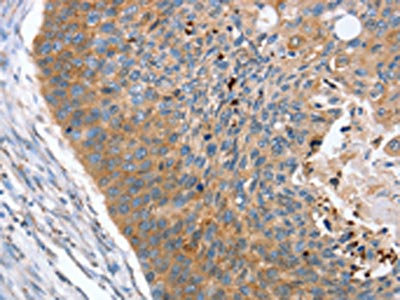

The image on the left is immunohistochemistry of paraffin-embedded Human esophagus cancer tissue using CSB-PA094733(REG3A Antibody) at dilution 1/40, on the right is treated with synthetic peptide. (Original magnification: ×200)